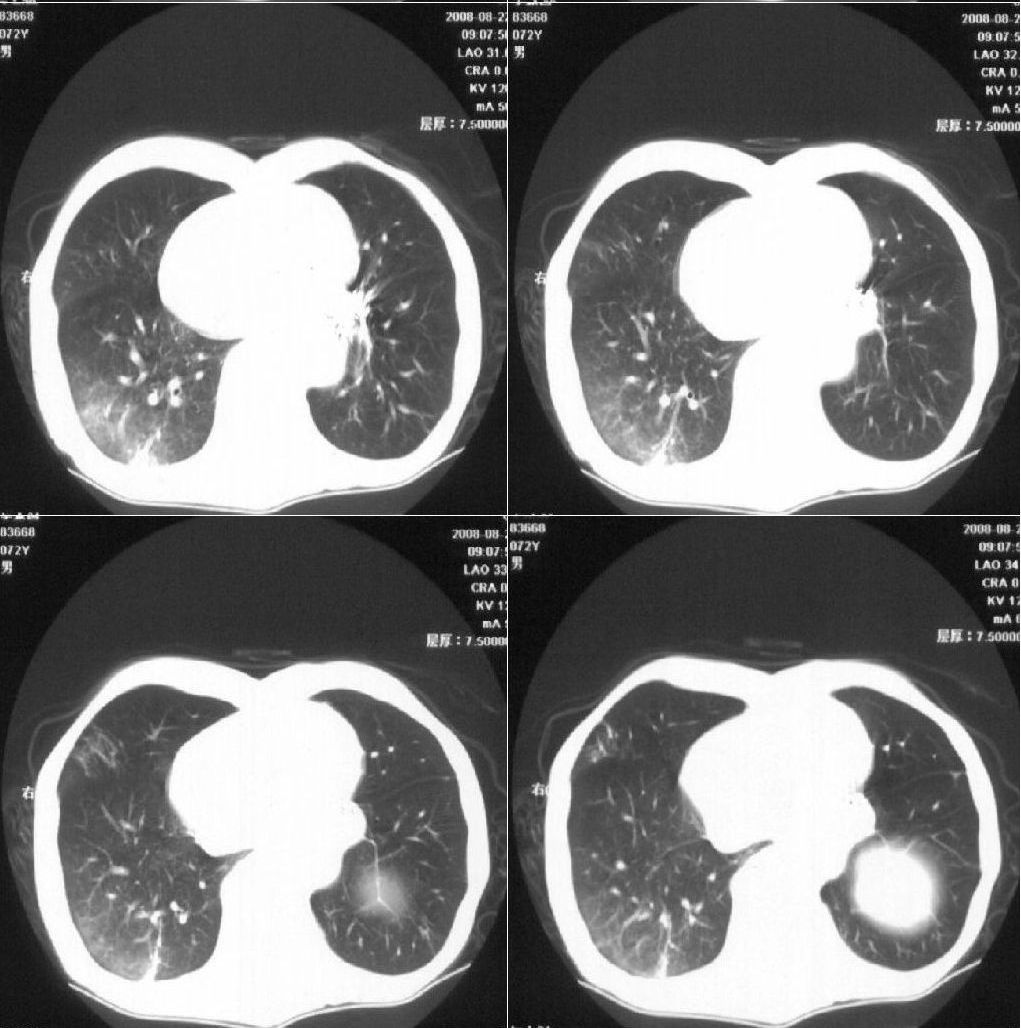

标题: CT15789:男性,72岁。食管癌术后14年。 [打印本页]

标题: CT15789:男性,72岁。食管癌术后14年。

痰培养:见葡萄球菌,霉菌少量生长。(此片系外院所作,仅提供了增强后的ct值为100hu,中心的坏死部分无强化,患者现在身体状况欠佳,为恶液质状态)

注意排外食管支气管瘘引起的肺部感染

周围型肺癌可能性大.

考虑右肺下叶感染性病变(肺脓肿?);建议抗炎治疗后复查。

符合机遇性感染,真菌可能性大。